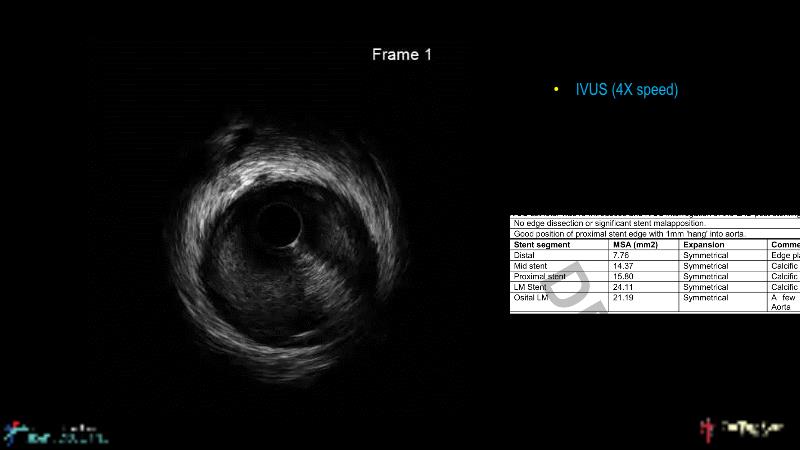

• To understand why the use of IVUS imaging is different from seeing with experienced eyes to achieve improved left main bifurcation outcome

• To know how a high radial strength stent can make a difference in left main bifurcation